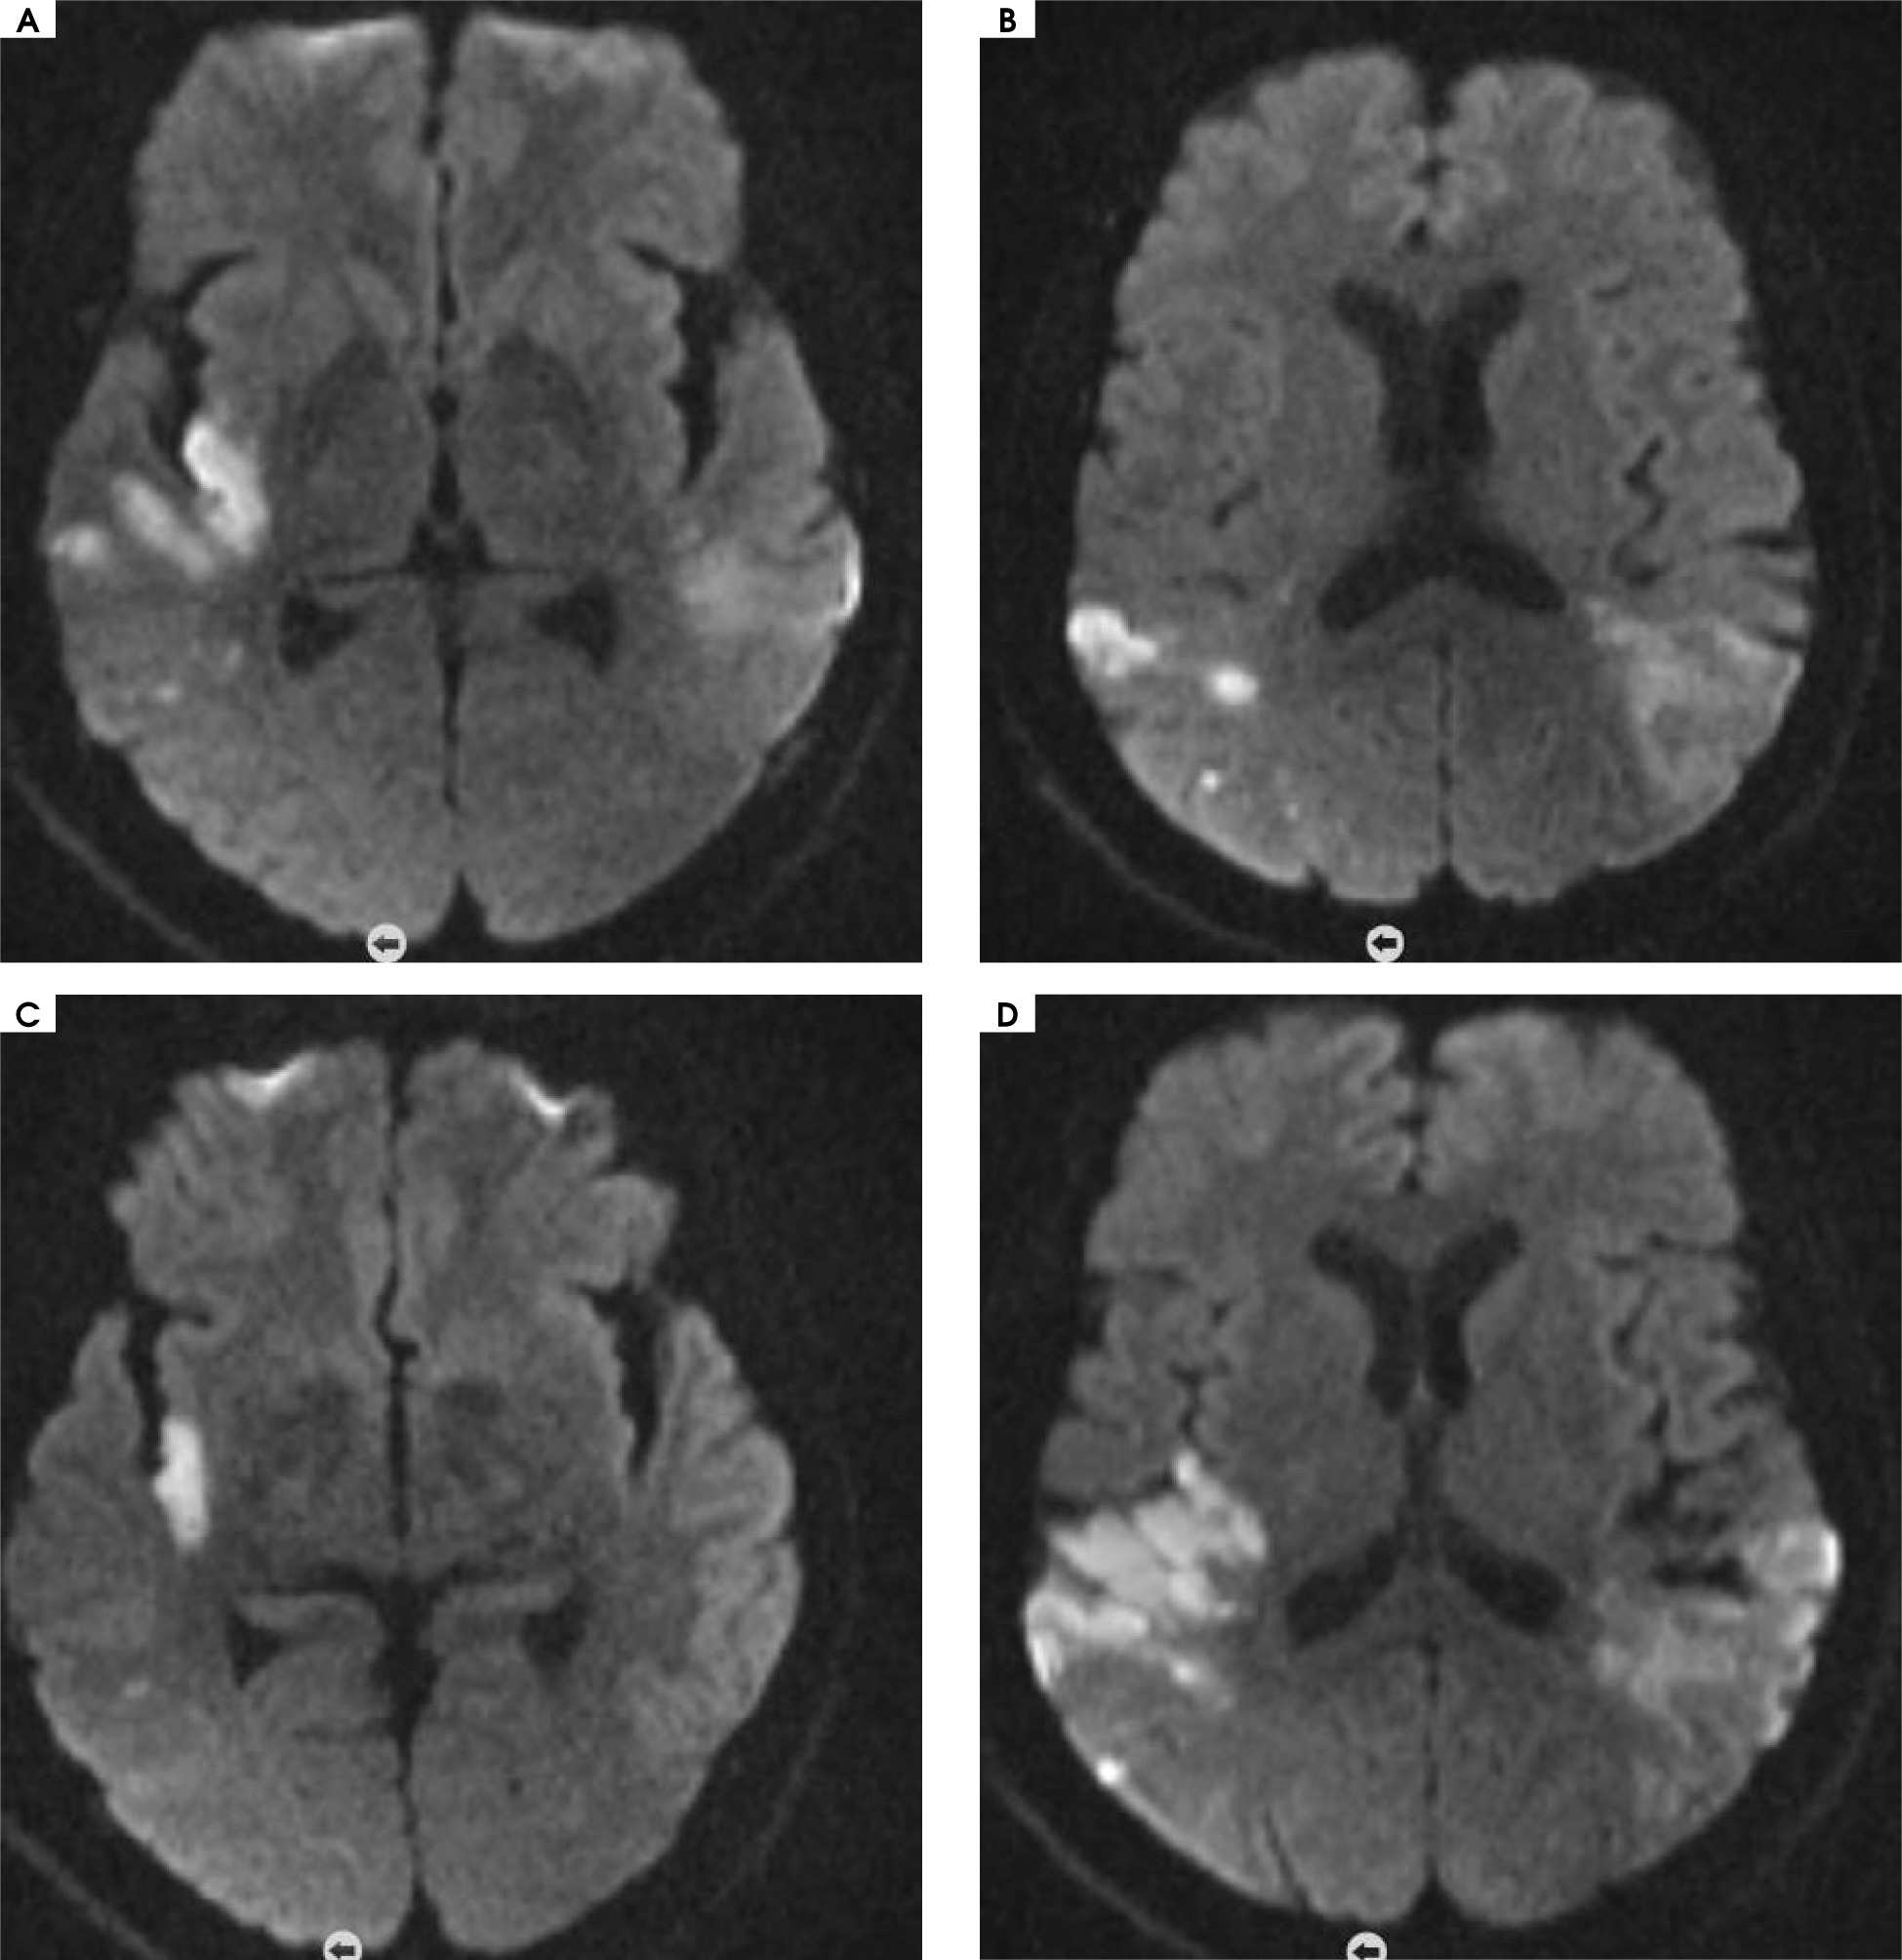

No evident acute pathology was detected in the brain computed tomography (CT) taken in the emergency department. In the brain magnetic resonance imaging (MRI) taken in the emergency room, diffusion restriction suggesting acute infarction in the right temporoparietal junction and findings suggesting acute-subacute infarction in the left parietotemporal junction were observed (Figure 2).

Figure 2

Acute and subacute infarction in the right temporoparietal junction and left parietotemporal junction